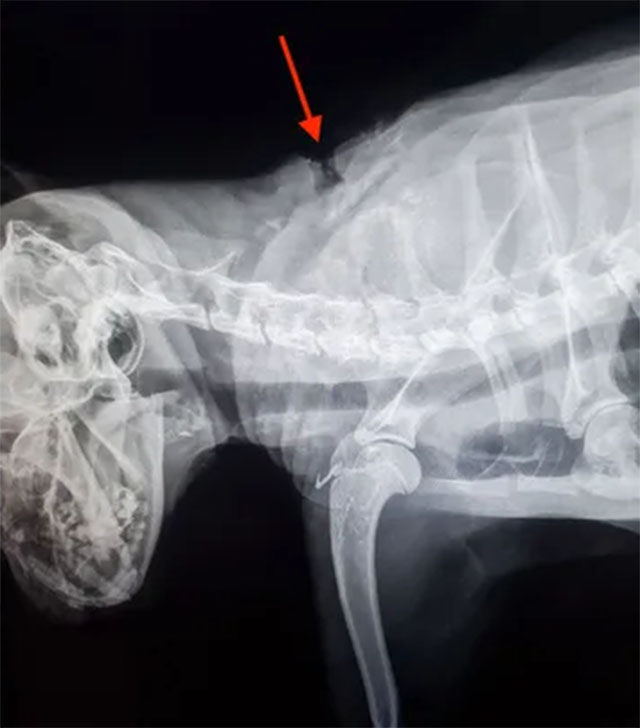

Veterinarians quickly assessed the extent of his injuries. The arrow had entered through his left shoulder and traveled across his neck in a way that, incredibly, missed vital arteries, major nerves, and even his spinal cord. While the physical trauma was significant, the fact that he had survived such an injury was nothing short of extraordinary. As Dr. Arielle Schoenlein later explained, it was a narrow escape that few animals would have endured.